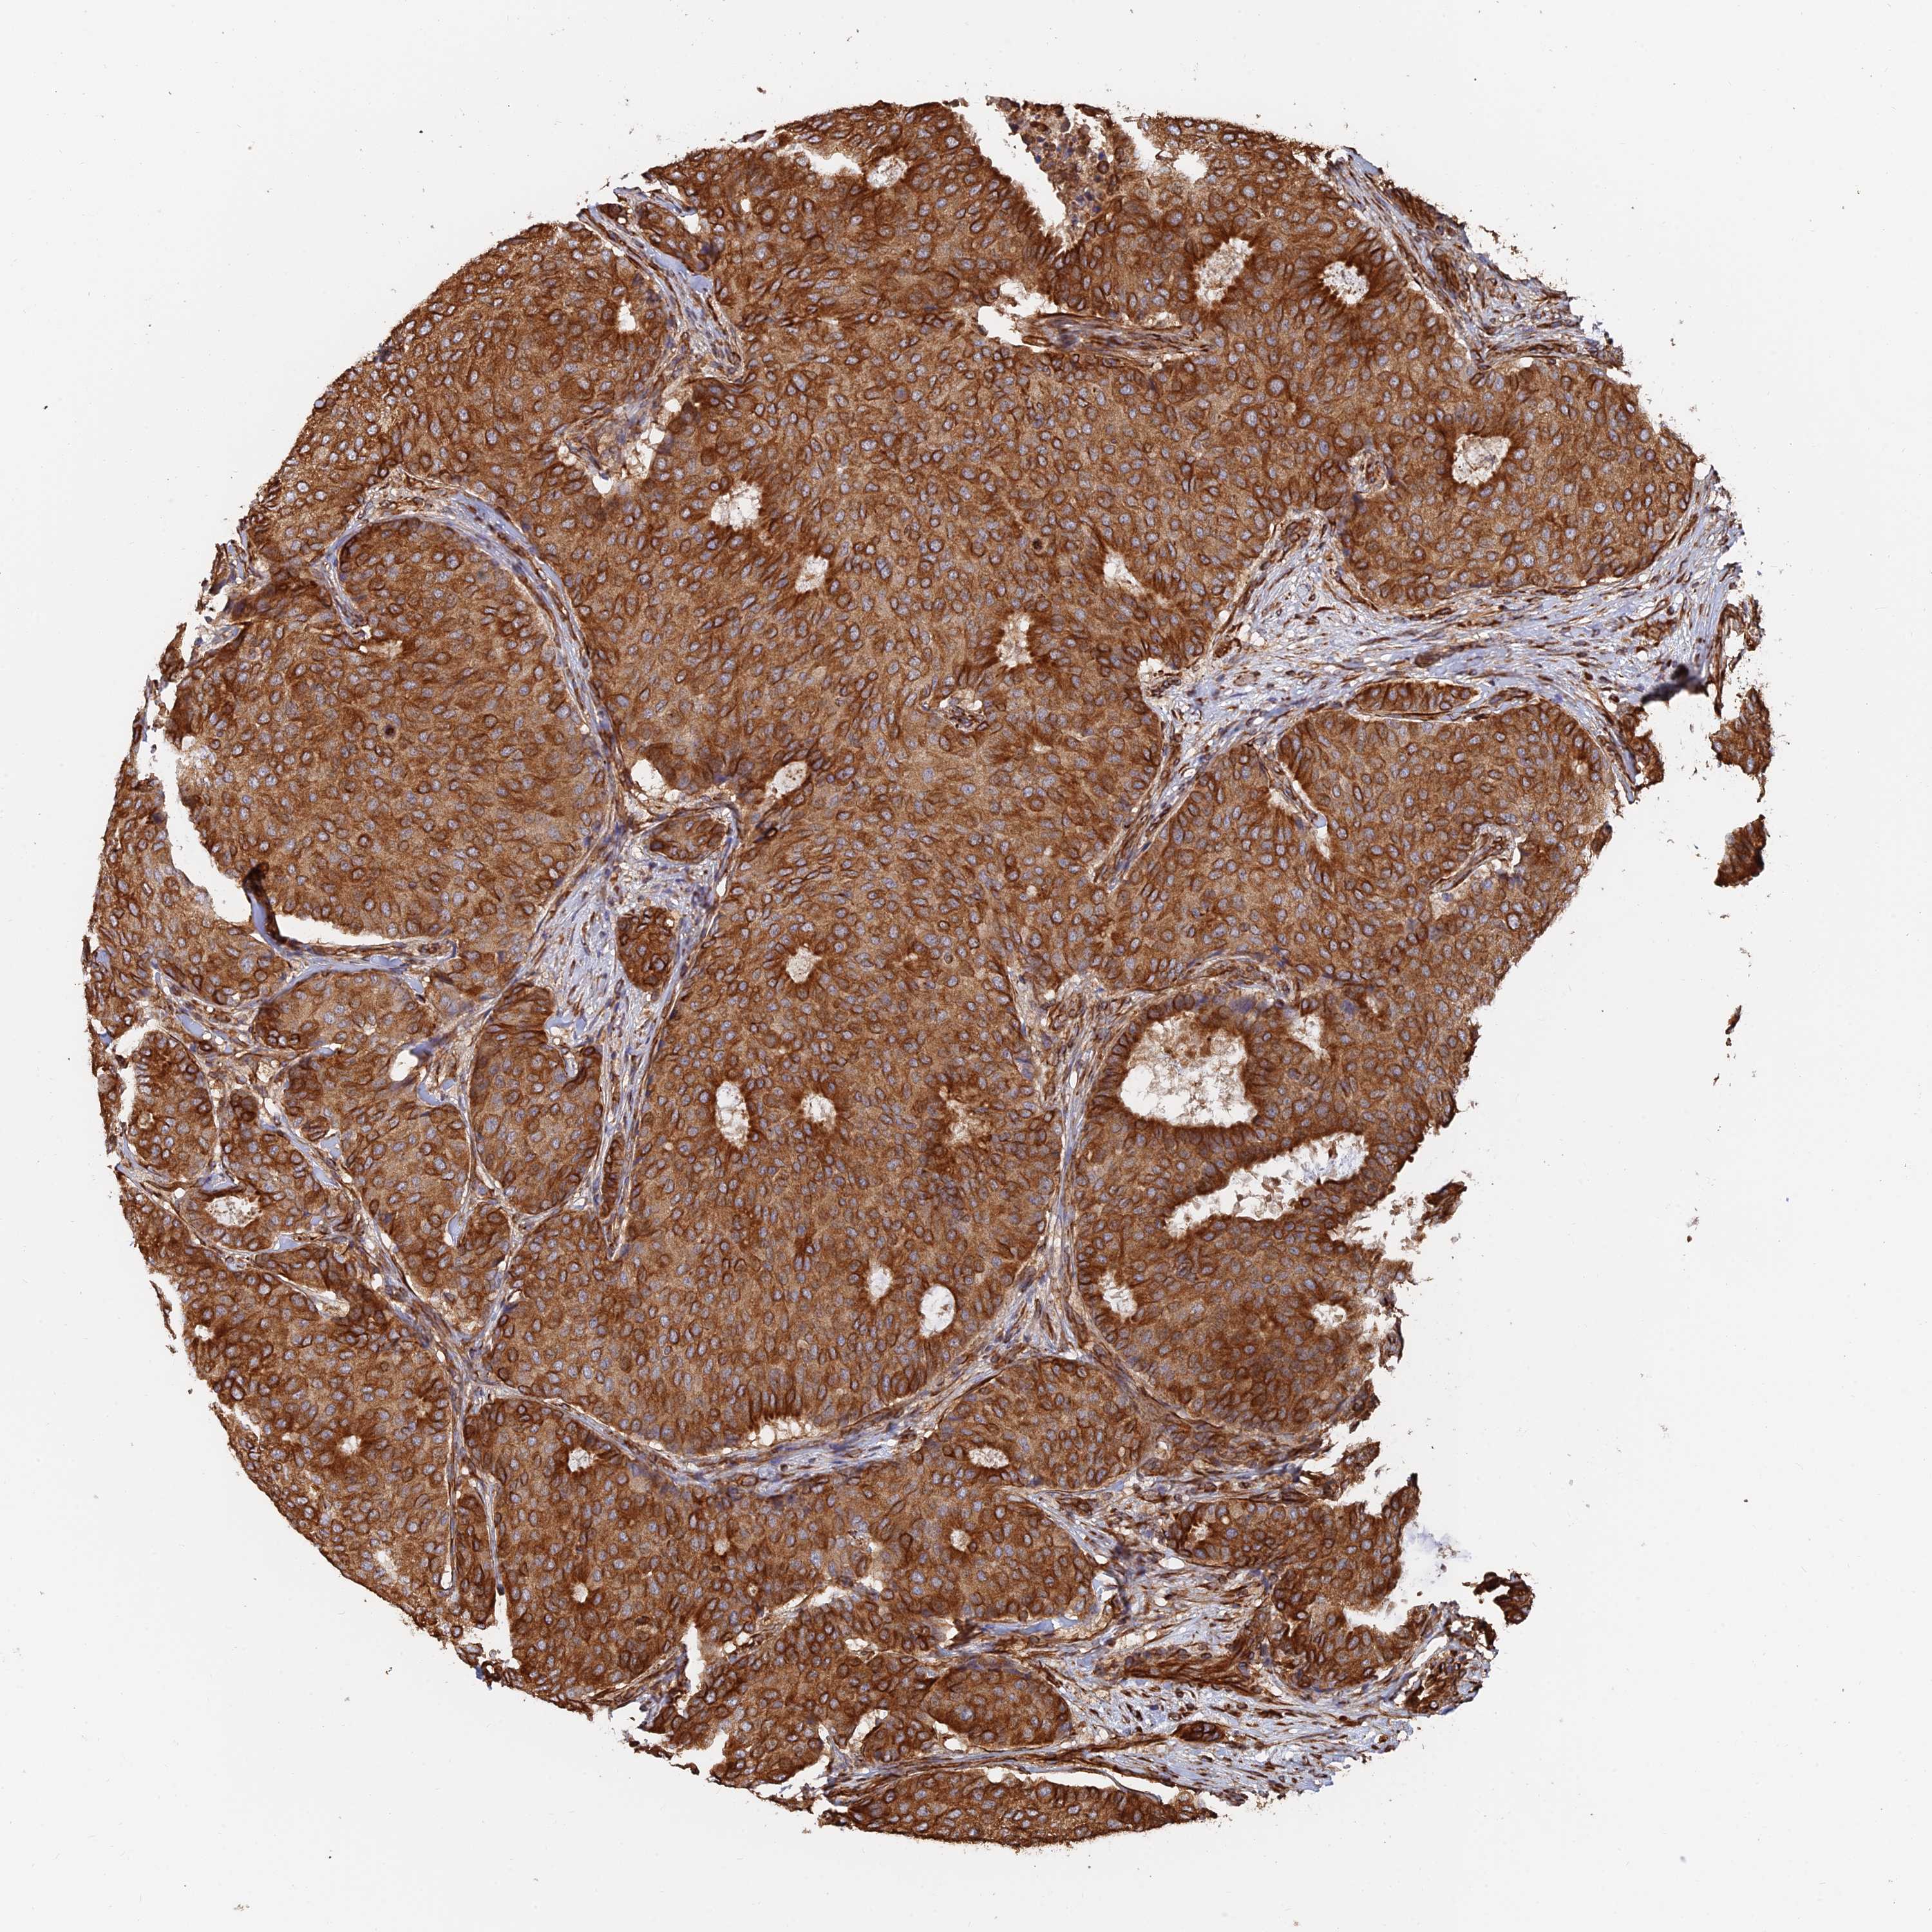

BRCA TCGA BRCA VALIDATION PROTEIN EXPRESSION

ANTIBODIES

AND

VALIDATION